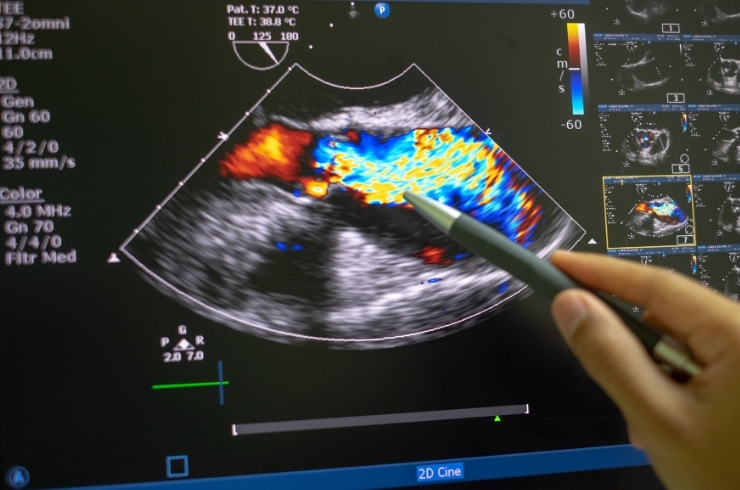

Intraoperative Echocardiography is a diagnostic imaging technique performed during heart surgery. It uses ultrasound—often via a probe placed in the esophagus (Transesophageal Echocardiography)—to give detailed, real-time views of the heart, helping surgeons assess the effectiveness of procedures like valve repairs or congenital defect closures.

• Provides immediate feedback during cardiac surgery

• Detects residual defects or complications on the spot

• Ensures precision in valve or structural heart repairs